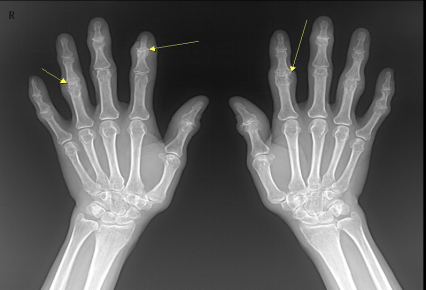

类风湿性关节炎

多发性、非特异性慢性滑膜炎症为主要表现的全身性疾病

多见于20-40女性

受累关节多呈对称性,以手足小关节为主

影像表现:①关节软组织肿胀;②关节间隙变窄、关节面边缘骨侵蚀;③软骨下多发囊样透亮区;④骨质疏松;⑤ 关节畸形和关节强直

F,55Y